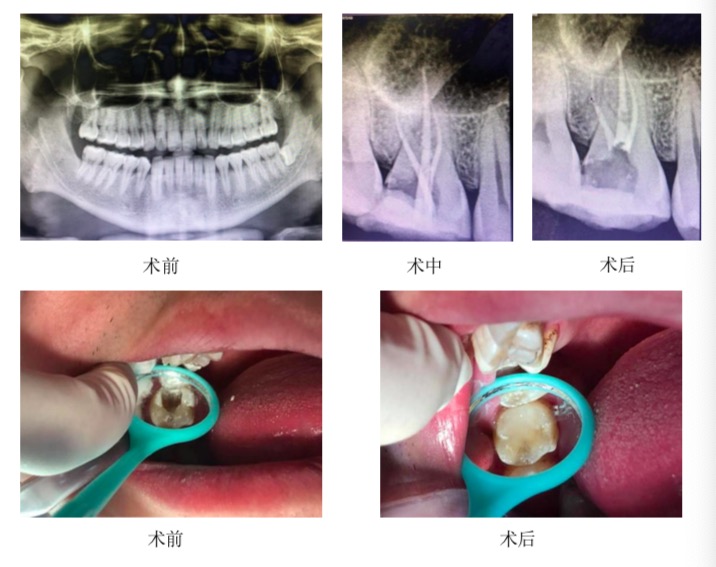

前段时间,苏州口腔医院张晓敏医生接到了一名28岁男性患者,他的右上后牙疼痛数月余,冷热刺激痛,吃东西也很痛,检查发现牙齿16(16为牙齿号数)远中邻面龋坏,最终选择了对16牙进行了根管治疗,复查后根尖区未见明显异常。

【根管治疗过程】:16第一周先去腐、开髓、封失活剂;第二周进行根管预备,封氢氧化钙消毒,暂封一周;第三周行根管充填,树脂恢复牙体外形。观察一周后若无不适行冠修复。